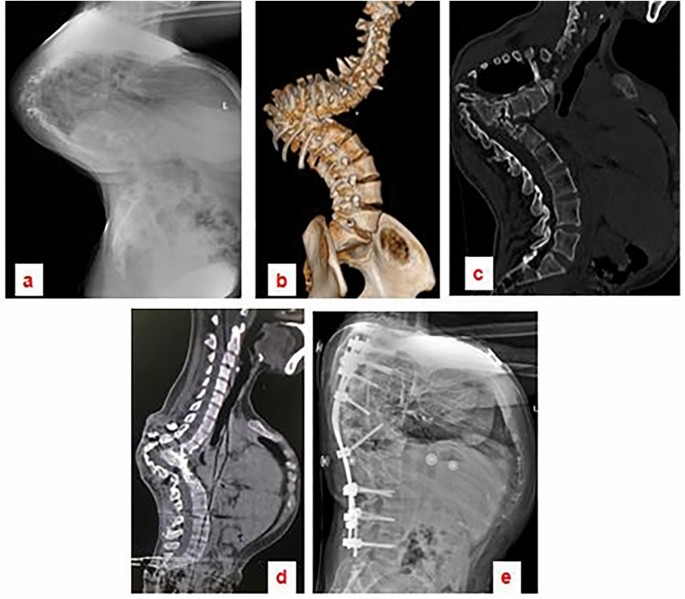

The surgical procedure averaged 492 ± 127.3 min in duration, with blood loss averaging 1791 ± 788.8 ml (range: 800–3000 ml). The follow-up period lasted 31.2 ± 5.49 months (range 24–42 months). The mean kyphotic angle experienced a substantial reduction postoperatively, descending from 97.6 ± 14.6° to 28.8 ± 18.70°, which constitutes a 65% correction rate. The lesions were localized to the lumbar spine in two patients, with a span from L1 to L5 in one case and from L2 to S1 in another. For the remaining patients, thoracic spinal lesions were identified. A three-column osteotomy was performed on the vertebra located below the apical region in 14 cases (Fig. 3), and above the apical region in two cases (Fig. 4). The respective preoperative kyphotic angles of these two patients were 85° and 61°, with postoperative lordosis angles recorded at 13° and 10°, respectively (Time scale analysis: − 13 and − 10). Post-surgical SVA readings indicated an improvement from 6.7 ± 3.58 to 3.3 ± 1.57 cm, effectively restoring the overall sagittal alignment of the spine, as detailed in Table 1. Neurological function was enhanced in six patients, whereas no substantial change was noted in the remaining ten at the final evaluation (Table 2).

29-year-old female patient with severe sharp angular kyphosis due to Pott’s disease. The tuberculosis lesion extended from T4 to T12. Image (a) is a lateral radiograph of the entire spine. Images (b and c) are 3D computed tomography (CT) scans illustrating the pronounced sharp angular kyphosis. Image (d) demonstrates that, following six months of halo-pelvic traction, there was a notable correction of the compensatory curve; however, the sharp angular kyphosis persisted. Image (e) is a postoperative lateral radiograph showing that a satisfactory correction was realized after performing an osteotomy at the L1 level.